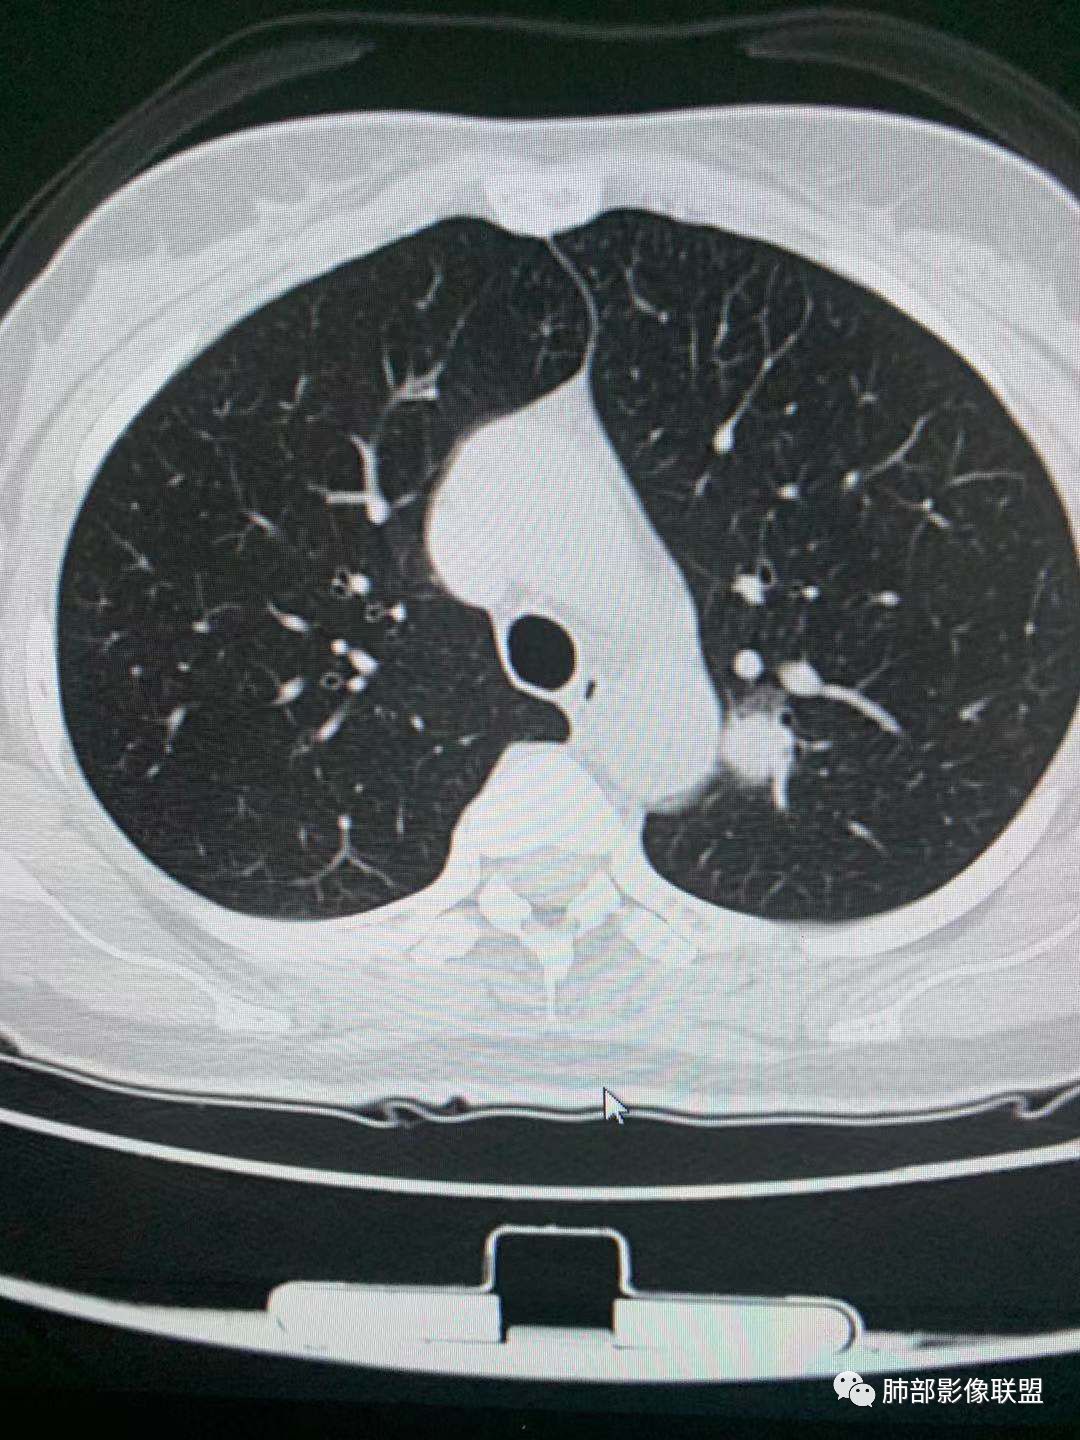

中年女性,体检发现。胸部CT示左肺上叶尖后段结节,边界清楚,边缘无分叶,邻近支气管无受压及阻塞;纵膈窗显示结节密度均匀,增强扫描中度渐进性均匀强化,未见坏死及空洞,考虑良性。结节周围可见磨玻璃晕征,并见血管贴边征,考虑硬化性肺细胞瘤(PSP)。

左肺上叶前段可见一磨玻璃结节,边界清,可见小叶间隔阻挡、毛刺 、胸膜牵拉,考虑微浸润腺癌。左肺上叶尖后段可见一实性结节影,边缘光整,光滑浅分叶,周围可见晕征,增强扫描明显延迟强化,可见血管贴边征,结节内未见气管及血管影,女性,考虑PSP

45岁女性,无症状。CT:左上叶前段见一小磨玻璃结节,边请,似有毛刺,边缘见月芽铲,考虑AIS→MIC可能;左上叶尖后段见一圆形实性结节,边清,无分叶,见血管及支气管贴边,增强后延迟强化,考虑良性结节,PSP可能性大,稍不放心的地方局部边缘见边界清楚的磨玻璃影,注意鉴别恶性肿瘤。

一.尖后段高密度大结节:

1.左肺上叶尖后段较大类圆形实性密度结节影,密度均匀,中等程度强化。

2.实性密度区边缘相当清楚,表面欠光整,偶见毛刺、棘突和旁出血管结构,未见典型的深分叶及邻近胸膜凹陷。

3.可疑支气管进入受阻。可惜缺乏连贯图像或冠矢状位以资判断。

4.病灶与胸膜之间有连线,邻近段支气管及肺血管整体后移,提示病灶还是有一定收缩性。

如上,单就这实性结节,硬化性肺细胞瘤(PSP)和腺癌似乎都能够解释,形态太规整了一些。

5.病灶周围见边界清楚的磨玻璃影,有点醒目,有点意外!

这是无论如何不能忽视的征象!

这点强烈提示,要么整个病灶恶性(腺癌),要么良性病灶旁滋生恶性病灶。

两年前左上肺的病灶什么位置,什么模样,是否相关?我们不得而知。